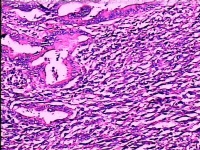

贲门腺癌的组织学类型主要有二类:腺癌与有明显粘液分泌的粘液腺癌。此二类又根据分化程度各自分为高分化、低分化和弥漫型三个亚型。分化程度之高低与手术预后关系密切。除了腺癌与粘液腺癌、贲门癌还有一些少见的组织学类型,如腺鳞癌、未分化癌、类癌(嗜银细胞癌)以及癌肉瘤等。